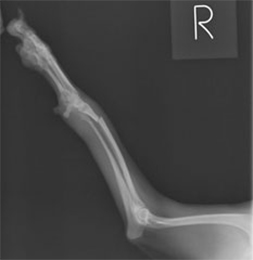

前肢上腕骨骨折

このタイプの骨折は猫、特に外に行く猫ちゃんに多く、高い所から飛び降りて着地に失敗することで骨折することが多いです。

手術前

手術後

この箇所の骨折は筋肉が多く、強度の高い固定が必要です。また今回みたいな斜骨折が多く認められます。髄内ピン、スクリュー、ワイヤーで治療を行いました。